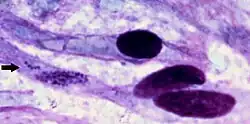

| Ehrlichia ruminantium bacteria within cell of brain of sheep that died of heartwater in Africa. | |

Heartwater (also known as cowdriosis, nintas, and ehrlichiosis) is a tick-borne rickettsial disease.[2] The name is derived from the fact that fluid can collect around the heart or in the lungs of infected animals.[3] It is caused by Ehrlichia ruminantium[4] (formerly Cowdria ruminantium)—an intracellular Gram-negative coccal bacterium (also referred to as Rickettsia ruminantium). The disease is spread by various Amblyomma ticks, and has a large economic impact on cattle production in affected areas. There are four documented manifestations of the disease. These are acute, peracute, subacute, and a mild form known as heartwater fever. There are reports of zoonotic infections of humans by E. ruminantium, similar to other Ehrlichia species, such as those that cause human ehrlichiosis.[5][6][7]

On post mortem examination, a light yellow transudate that coagulates on exposure to air is often found within the thorax, pericardium, and abdomen. Most fatal cases have the hydropericardium that gives the disease its common name. Pulmonary oedema and mucosal congestion are regularly seen along with frothy fluid in the airways and cut surfaces of the lungs. To definitively diagnose the disease, C. ruminantium must be demonstrated either in preparations of the hippocampus under Giemsa staining or by histopathology of brain or kidney.